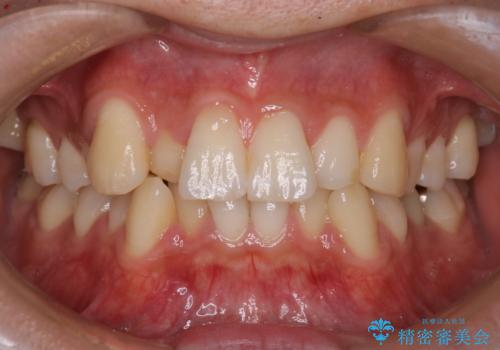

前歯のガタガタを治したい。

- 凸凹を治したいと来院された患者様です。

インビザラインにて、遠心移動を行いながら綺麗に配列することができました。